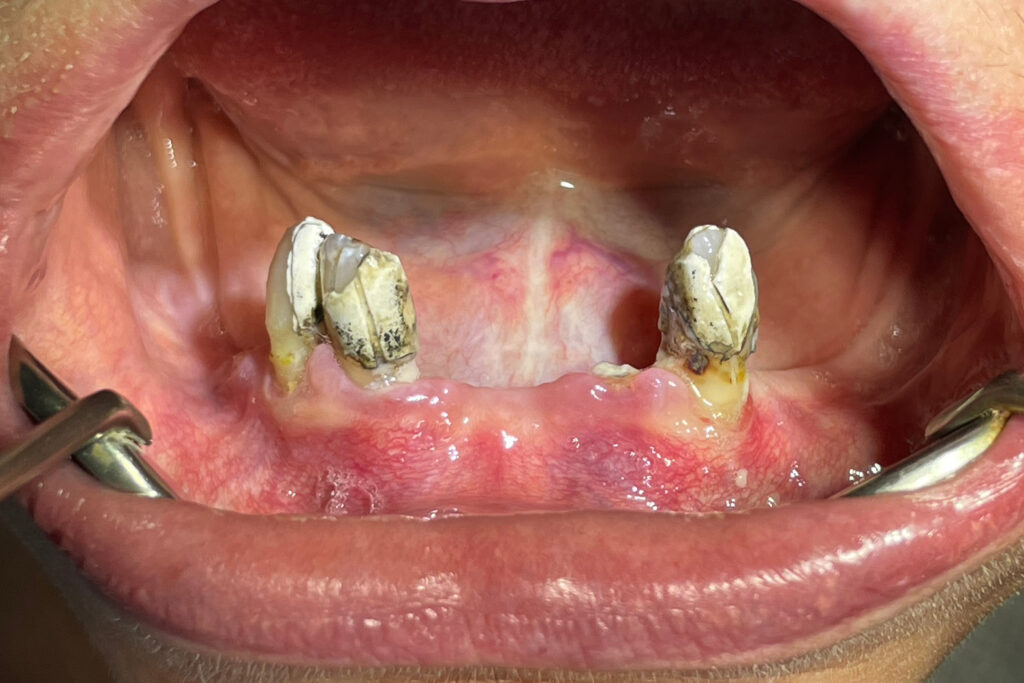

Ситуация до лечения

Жалобы: Пациент обратился к нам с целью изготовления съемных протезов после консультации в сторонней клинике.

Диагноз: Полная адентия верхней челюсти и частичная вторичная адентия нижней челюсти.

пациент до имплантации

После проведенной консультации было принято решение об удалении зубов на нижней челюсти, которые находились в неудовлетворительном состоянии и проведении комплексной имплантации по системе All-on-4.

На верхней челюсти было принято решение изготовить съёмный акриловый протез.